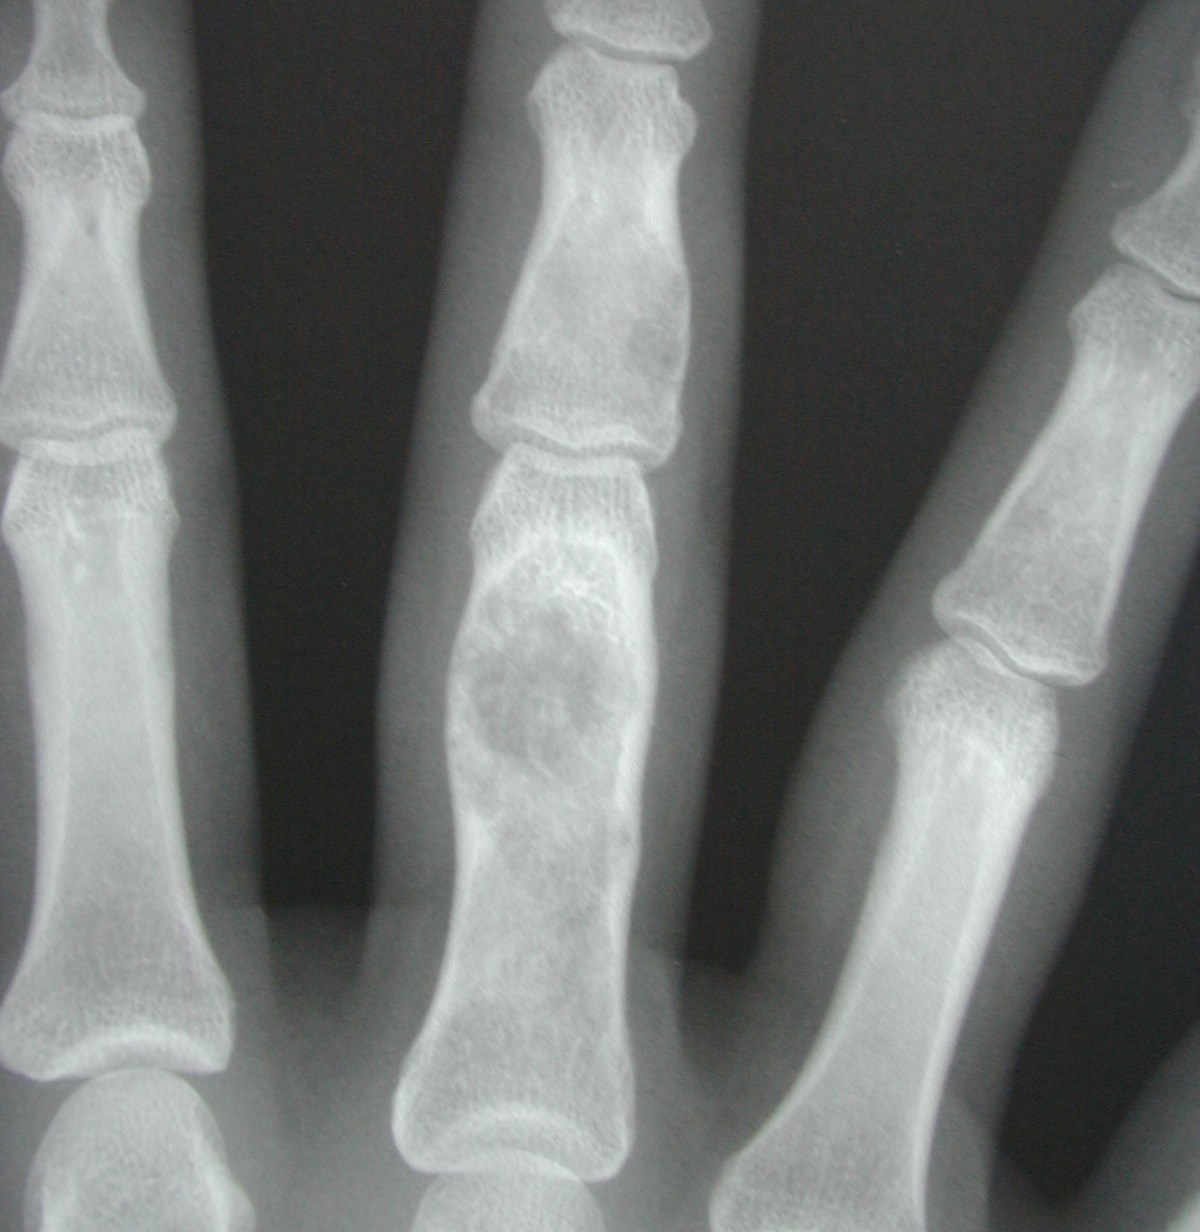

Enchondrom